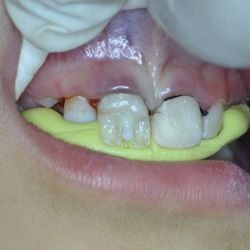

This young lady came to our practice complaining about her chipped upper incisors.

Using Nano technology composite resins, we were able to restore the shape of her front teeth and give her smile back.